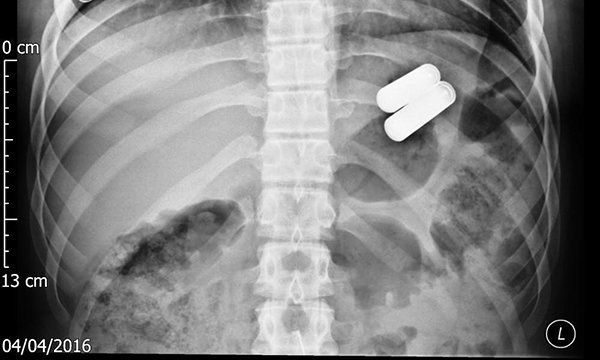

Foreign body ingestion and foreign body aspiration commonly affect children. The most vulnerable age is between six months and four years, when children tend to explore new objects with their mouths. Many of these events remain asymptomatic, with the swallowed object passing through the gastrointestinal tract without causing harm. However, the frequency of serious complications as a result of the ingestion of hazardous objects has increased in recent years, in particular button batteries and magnets. To increase the likelihood of identifying foreign body ingestion and aspiration, healthcare professionals should maintain a high index of suspicion, be aware of the variation in presentations and include it as a differential diagnosis in children presenting with non-specific symptoms, such as fever, cough, drooling, dysphagia and abdominal pain. Management of most foreign body ingestions is conservative, using a ‘watch-and-wait’ approach. Children should be triaged as an emergency if they have signs or symptoms of airway obstruction or a history that indicates dangerous foreign body ingestion. Early recognition and management leads to improved outcomes for patients. Nurses have a vital role in providing education and practical advice to parents, which reduces the occurrence of these events. Stronger legislation is required to ensure manufacturers emphasise the potential dangers of certain products and design child-safe devices.